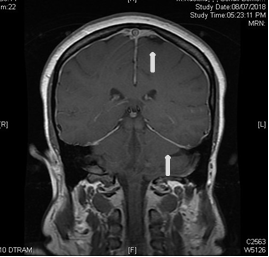

She had MRI brain and C spine with contrast, (Figure 1) a lumbar puncture after imaging, intravenous pain medication, dexamethasone per os, and was positioned supinely. Her brain MRI and C spine showed signs of low intracranial pressure with DME; see in Figure 2. She initially had a traumatic and dry LP with Glucose 5.68, raised protein of 3672 mg, 54000 red cells, 43 white cells and xanthochromia was positive.

Figure 2 white arrows pointing to contrast enhancement.